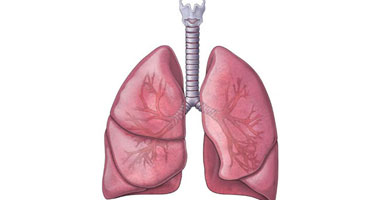

ما وظيفة الرئتين بجسم الإنسان اليوم السابع

وظائف الرئتين الرئة البشرية البنية الوظيفة الدواء 2020

أكبر أعضاء جسم الإنسان تعرف عليها ويب طب

أين تقع الرئتين في جسم الإنسان موضوع

8 نصائح لتحسين صحة الرئتين أبرزها التنفس العميق اليوم السابع